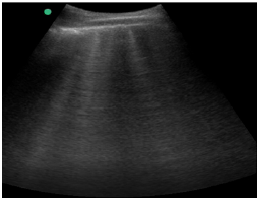

Um paciente de 50 anos de idade encontra-se, internado na UTI por conta de choque séptico de foco pulmonar, em ventilação mecânica na modalidade pressão e no modo assisto-controlado. Pela manhã foi submetido a acesso venoso central em veia axilar guiado por ultrassonografia. Ao exame físico, notou-se que o paciente está com hipotensão e taquicardia. A primeira hipótese diagnóstica é pneumotórax e é realizada radiografia com imagem apresentada.

Qual imagem abaixo corresponde ao achado ultrassonográfico para o paciente em questão?